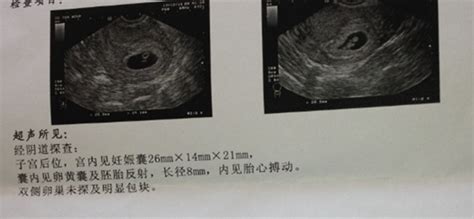

怀孕8个月的B超数据

根据孕周表,您的宝宝双顶径和骨长,也就是头部横径和大腿骨长都发育正常,胎心和羊水深度也在范围值内,脐带血阻比也正常。

怀孕八个月B超结果如下:双顶径80mm.胎心率132次/分,股骨长59mm,羊水深约61mm,内透声好。胎盘附于子宫前壁,厚约28mm,绒毛板轻度起伏。这样正常吗,知不知道有几斤?谢谢

31周左右,一切正常!